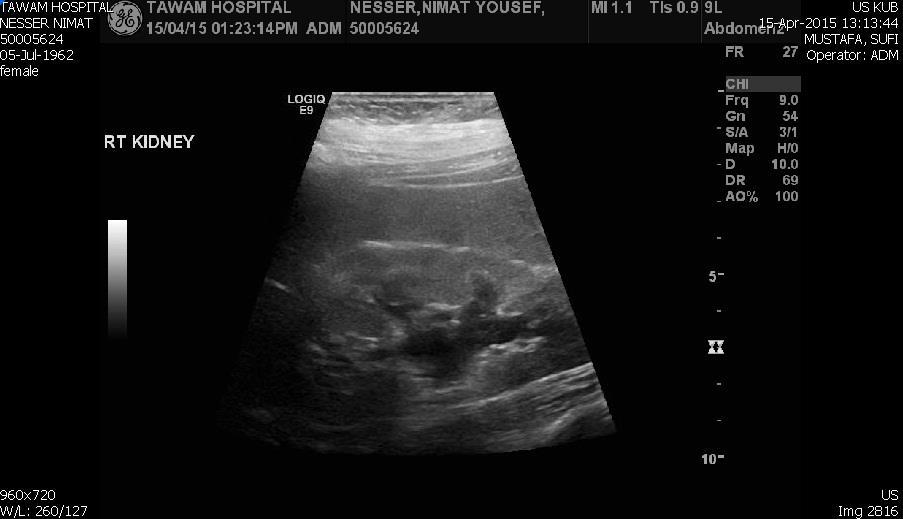

Blood tests on April 14th showed: Na = 131, K = 5.1, Urea = 6.9, S. Creatinine = 96, and eGFR = 61ml/min. Urine analysis and cultures confirmed E. coli urosepsis, blood cultures were negative. Renal US revealed echogenic kidneys, mild bilateral hydronephrosis of about 12 mm with normal ureters and urinary bladder (Figure 1 and Figure 2). Treatment with oral antibiotics resulted in improvement of temperature and dysuria. On April 20th patient seen by endocrinology and nephrology because of persistent back pain, dapagliflozin was discontinued and followed by resolution of symptoms in few days. Patient had two kidney ultrasounds in May and June, both indicated gradual resolution of bilateral hydronephrosis. Repeat CT of the abdomen on July 7th revealed complete resolution of hydronephrosis (Figure 3). Most recent eGFR is 72 ml/min.

Figure 1.Right kidney hydronephrosis